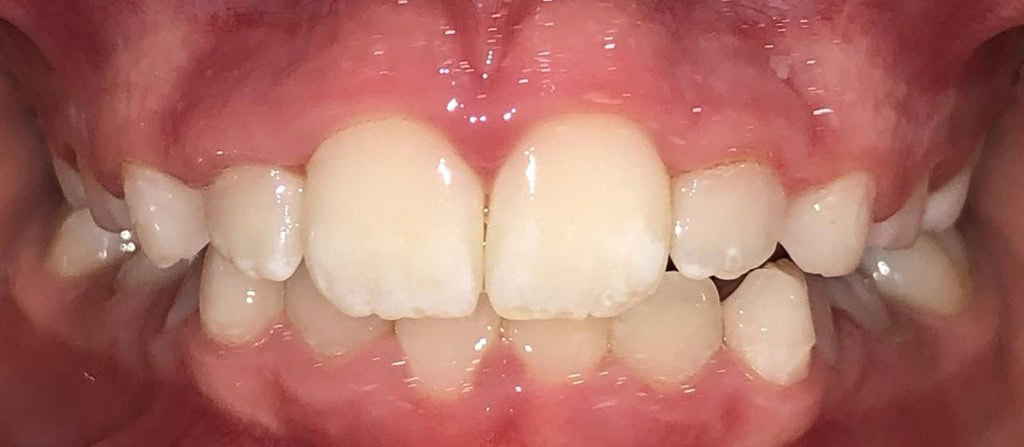

Actual Patient: Alexander

Alexander Before 4 Alexander After 4

Severe “Underbite”, Narrow Jaws, Adult Teeth Not Growing In

Alexander Before 1 Alexander After 1

Front View

Top View

Right & Left Sides

Side View Results

0 Month

6 Month

11 Month